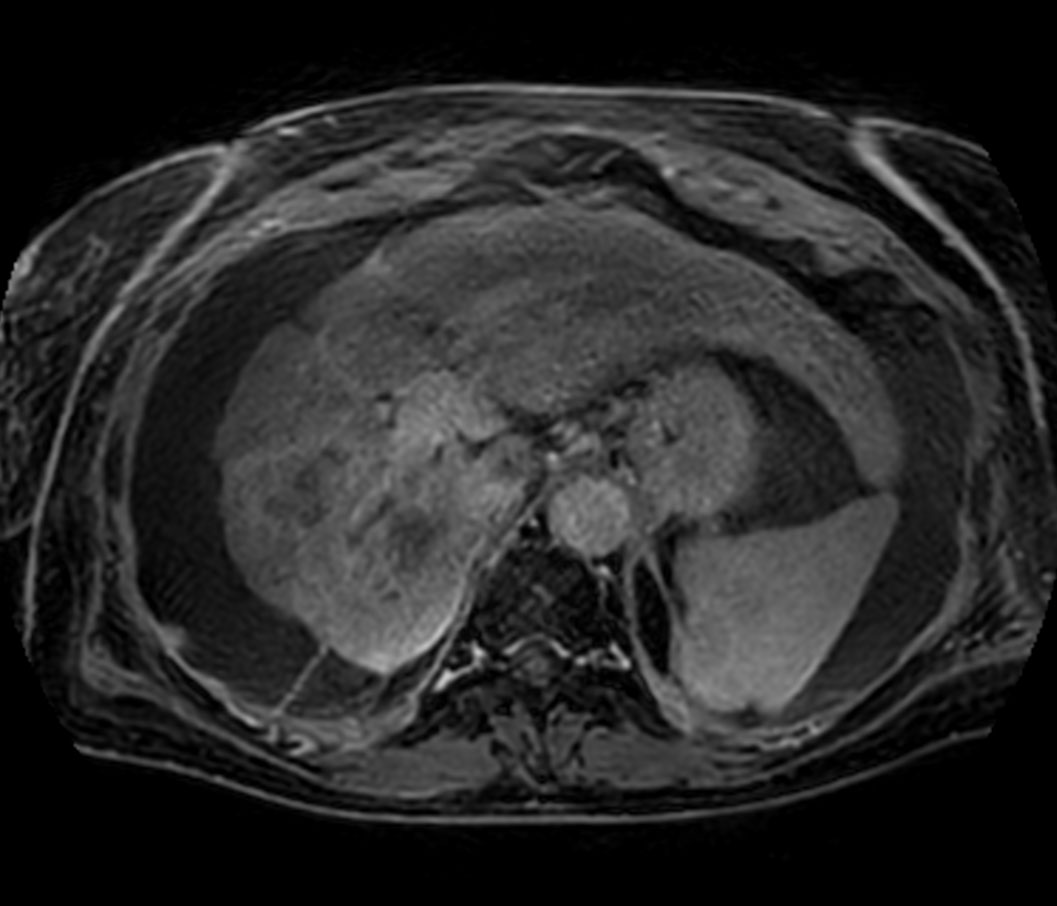

Axial Diffusion - b0